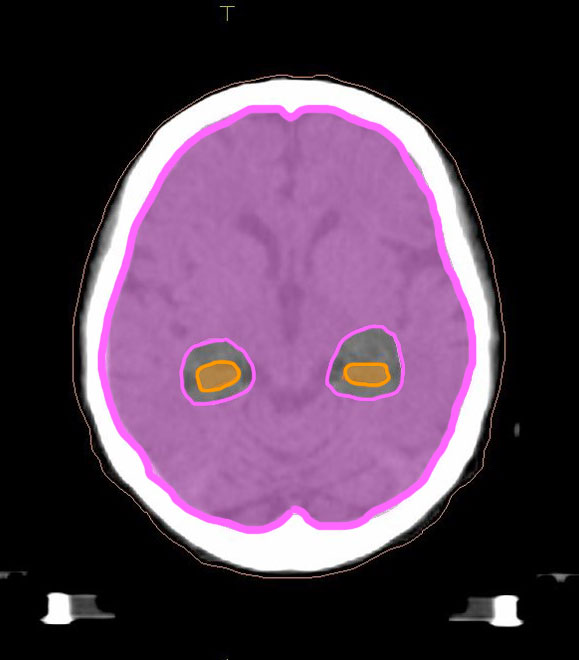

海馬回避全脳照射イメージ

海馬(オレンジ部分)部分を避けた照射対象(ピンク部分)